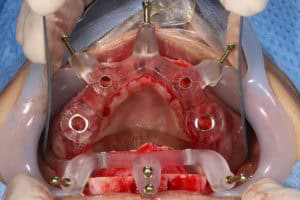

The main idea behind the static CAIS is rather simple: create an acrylic “template”, which will guide our drills to the perfect osteotomy and then place the implant accordingly. It is based therefore on a 3D printed surgical guide with “sleeves”, which allow the placement of the drills controlling angle and position and “stops” to control the depth. The guide can be supported on teeth, on oral mucosa, on the underlying bone through mini screws or a combination of the previous. It can be a single piece guide, or “stackable” in order to cover several procedures, such as for example a possible ostectomy prior to implant placement or a lateral sinus floor augmentation. But this is about where the principle ends and the application starts! Today almost every major implant brand has its own guided surgery software, instruments and overall protocol (Figure 2). The differences can be significant and this diversity is not based on evidence, but rather reflects each company’s philosophy, design, historical features and insider-view on implant surgery. Does it really matter? Well, evidence shows that it does. In a recent study we compared the precision of implant placement with 5 different commonly available guide designs and guided surgery configurations (3). The results showed significant differences, with the “sleeve in sleeve” guides achieving almost half the deviation than some of the “mounted” or “integrated” sleeve guides (Figure 2). At the same time, accuracy might be not the only parametre that is clinically important in a system. Ease of use by the surgeon, reliability of the full workflow, availability of a wide array of drills, sizes and components, durability and costs are also to be accounted for. As we begin to understand the implication of design parametres through proper research, guided surgery kits in the future might start to converge towards the best practices or principles which deliver the most. For now however, be mindful, there is not one such think as “static guided surgery protocol”, despite what some systematic reviews will try to convince you. On the contrary, there are many different protocols, with significant differences in results, potential and limitations. Choose wisely!